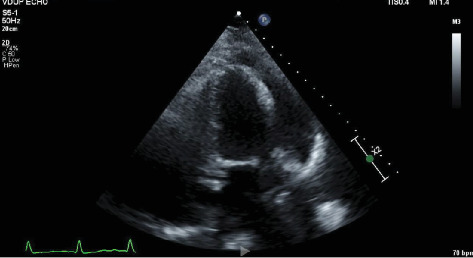

Hydralazine是一种常用的动脉血管扩张剂,用于治疗充血性心力衰竭和高血压,已知与药物性狼疮和抗中性粒细胞胞浆抗体(ANCA)相关血管炎(AAV)有关。药物诱导的AAV通常具有良好的长期预后,通常与心血管或眼部受累无关。与肼相关的心包炎病例以前未见报道。我们提出一个罕见的病例,涉及一名85岁的妇女长期服用肼,最初表现为急性大叶性肺炎。在住院期间,她出现心包炎、化脓和眼睛结膜炎,并伴有皮肤病变,包括面部丘疹、手指上的嫩嫩的大疱和背部的点疹。实验室结果与药物诱导的AAV一致,显示髓过氧化物酶和蛋白酶3抗体阳性。尝试诊断性心包穿刺失败。停用海拉嗪,她成功地用皮质类固醇治疗,免疫抑制耐受良好。随后,她康复出院。

Hydralazine, a commonly used arterial vasodilator for managing congestive heart failure and hypertension, is known to be associated with drug-induced lupus and, less frequently, antineutrophil cytoplasmic antibody (ANCA)-associated vasculitis (AAV). Drug-induced AAV typically carries a favorable long-term prognosis and is not commonly linked to cardiovascular or ocular involvement. Pericarditis cases associated with hydralazine have not been previously reported. We present a rare case involving an 85-year-old woman on long-term hydralazine therapy, initially presenting with acute lobar pneumonia. During her hospitalization, she developed pericarditis, chemosis, and conjunctivitis in her eyes, along with cutaneous lesions described as a maculopapular rash on her face, tender bullae on her digits, and a petechial rash on her back. Laboratory findings were consistent with drug-induced AAV, showing positive myeloperoxidase and proteinase 3 antibodies. An attempted diagnostic pericardiocentesis was unsuccessful. Hydralazine was discontinued, and she was successfully treated with corticosteroids and tolerated immunosuppression well. Subsequently, she recovered and was discharged from the hospital.